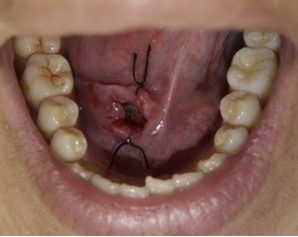

Se decide su tratamiento quirúrgico conservador siguiendo el protocolo de la técnica de marsupialización modificada. Bajo anestesia local (articaína 4%) con bloqueo directo del nervio lingual ipsilateral, se realizó la transfixión con hilo de sutura no absorbible seda 4,0 (Silk®) en la superficie de la mucosa del piso de la boca con los bordes de la lesión. Después de delimitar el campo se realizó una incisión aguda de la mucosa y cápsula a lo largo de su eje mayor (pared superior de la ránula). Con la incisión hecha y la retirada de la pieza para estudio histopatológico, se vació el contenido mucoso, permitiendo la resección de la parte superficial del quiste. Se introdujo con un elemento de contención impregnado con antiséptico intralesional (gasa impregnada en Furacín®) para que no colapse la cavidad quística, la cual se sutura en la periferia para impedir su desalojo con los movimientos (fig. 3). Se indicó irrigar la cavidad con clorhexidina al 0,12% 10 ml 2 veces al día por 10 días. Como tratamiento farmacológico se le indicó amoxicilina comprimidos 500 mg cada 8 h por 7 días, e ibuprofeno 600 mg cada 8 h por 3 días. Para su control y seguimiento se citó a los 3, 7 y 10 días (fig. 4). Al décimo día se eliminó el elemento de contención (fig. 5). Se realizó un seguimiento clínico por 12 meses, sin observarse signos de recidiva de la lesión (fig. 6).